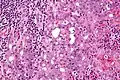

Very high mag.

Very high mag.

Histopathologic features

Basophilic, bland cells similar to acinar cells. Growth pattern: solid - acinar cells, microcytic - small cystic spaces mucinous or eosinophilic, papillary-cystic - large cystic lined by epithelium, follicular - similar to thyroid tissue.

These tumors, which resemble serous acinar cells, vary in their behavior from locally aggressive to blatantly malignant.

- Fine-Needle Aspiration Cytology (FNAC): Often the initial diagnostic procedure due to its minimally invasive nature. Characteristic cytologic features include:

- Abundant basophilic granular cytoplasm

- Small, round, eccentric nuclei with minimal atypia

- Acinar, microcystic, or papillary arrangements